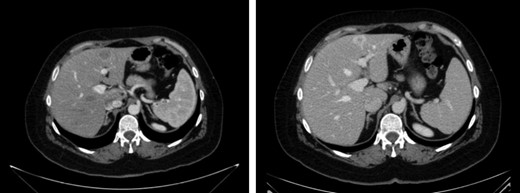

Finally, 12 months after this second liver surgery, a new hepatic lesion in left hepatic lobe of 3 cm was identified (Fig. 4). Systemic treatment was re-initiated with Cisplatin (75 mg/m2) and Cetuximab for 2 months. After that, left hepatectomy was performed with tumor-free surgical margins without subsequent complications. Surgical specimen revealed undifferentiated tumor.